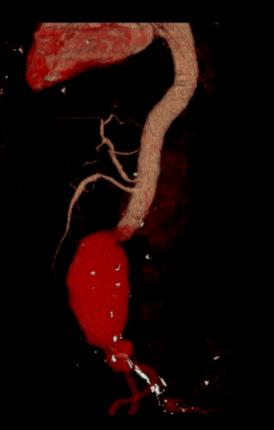

增强后:腹主动脉下段至左右髂总动脉上端明显扩张,最宽处约6.8cm,上下径约为13cm,成瘤样改变,边界清楚,形态规整。

1.腹主动脉瘤。(腹主动脉下段至左右髂总动脉上端)

后重建图像就是直观